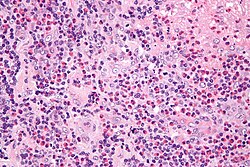

| Kikuchi disease (histiocystic necrotizing lymphadenitis) | No PMNs | histiocytes, necrosis | IHC for large cell lymphoma (CD30 + others) | SLE (has (blue) hematoxylin bodies in necrotic areas), large cell lymphomas | File:Histiocytic necrotizing lymphadenitis - very high mag.jpg HNL - very high mag. |

Kikuchi disease

Main article: Kikuchi disease